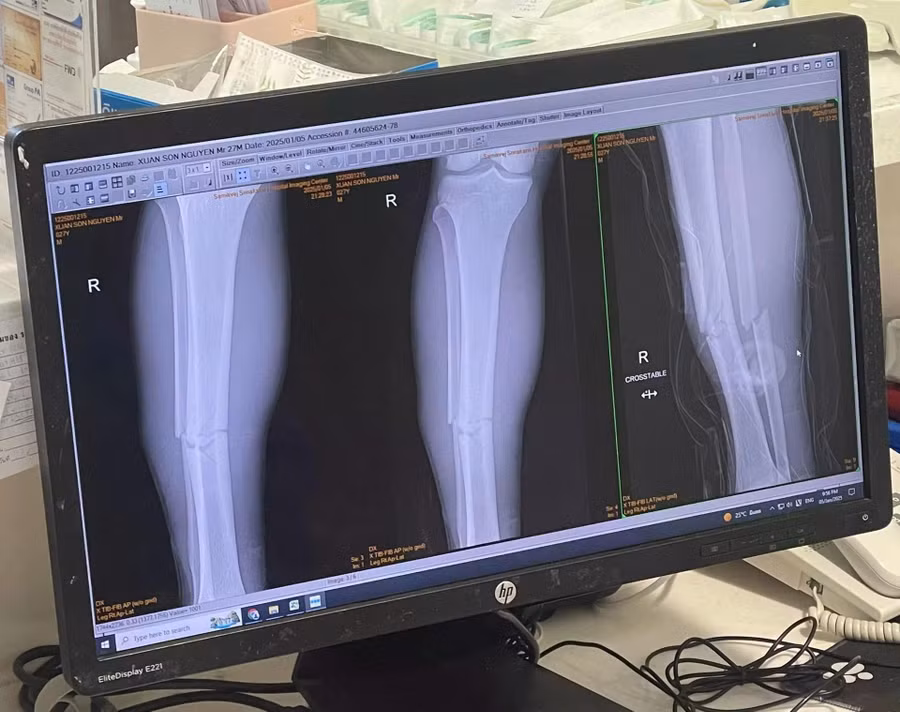

Xuân Son sau đó đã được đưa vào bệnh viện với kết quả chụp phim đã gãy cả 2 xương ở ống chân phải. Đây là chấn thương rất nặng, khiến cầu thủ sinh năm 1997 sẽ phải cần nhiều thời gian để trở lại.